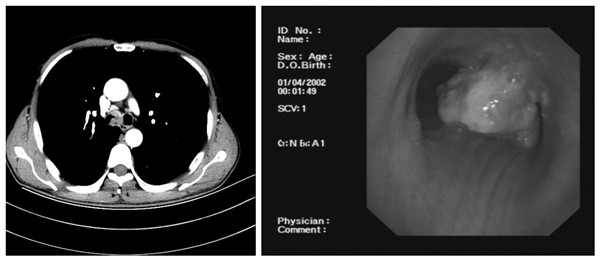

患者邵某某,男,55岁,以“咳嗽3月余”之主诉于2020年01月18日入住我院胸外科。入院后行胸部CT及支气管三维重建提示主气道肿物(图1),行气管镜检查提示处隆起性病变,延伸至左、右支气管,病理活检提示鳞状细胞癌。经过术前检查排除手术禁忌后李少民主任邀请急诊科、麻醉科等相关科室进行多学科会诊,遂决定行在ECMO支持下行气管肿瘤切除、隆突重建术。经过充分的术前准备,1月26日上午,在麻醉科团队进行全身麻醉后,急诊科团队立即进行VV-ECMO连接,确保患者术中血氧的维持,随后胸外科李少民主任、周斌教授、张晋副主任医师团队进行手术操作,术中见肿瘤位于气管隆突处,完整切除了肿瘤位置的气管及部分左、右支气管,长度约4cm,并成功完成主气管及左、右支气管残端吻合,手术过程顺利,术后患者生命体征平稳,顺利脱离ECMO、拔除气管插管后安全返回急诊科监护室,第二日转入胸外科普通病房,术后恢复顺利,于2021年02月04日出院。

图1